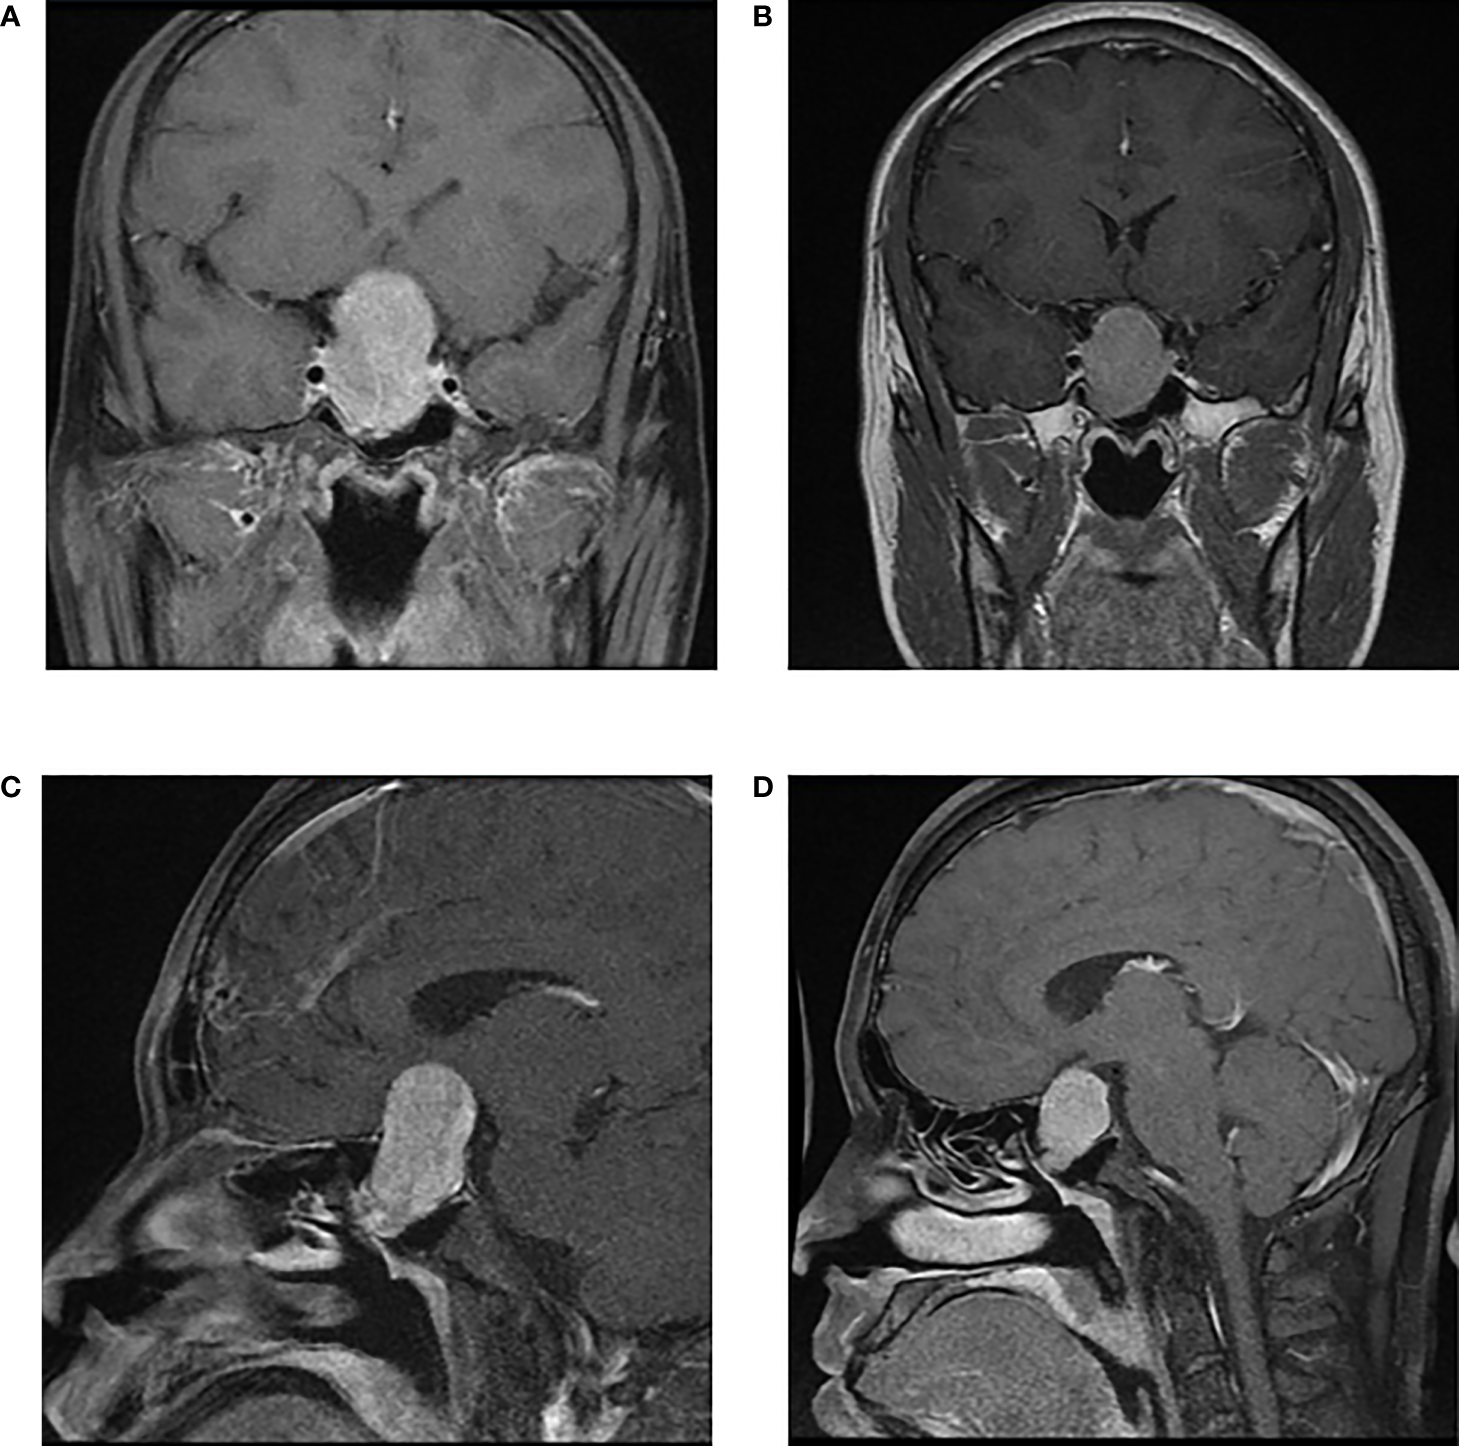

In the 26 patients with long- acting SSA, changes in the maximum tumor diameter on MRI before and after medication in a total of 12 patients with available data were compared which showed that long- acting SSA could shrink the maximum tumor diameter at a median of 1.0 (−1.6, 4.925) mm, in which 4 patients (4/12, 33%) had a maximum diameter reduced more than 5 mm, while 2 patients maintained a stable tumor volume although it revealed enlargement (less than 2 mm). A typical MRI image of before and after long-acting SSA use is illustrated in Figure 2.

Figure 2

A patient with macroadenoma (46.7×27.7×23.5mm) received long-term SSA (Sandostatin LAR) for 12 weeks and achieved tumor shrinkage (34.2×24.8×20.9mm). Thyroid functions reduced to normal ranges after 4 weeks of medication. However, tumor was in tough texture examined in surgery and rather hard to resect due to long duration of SSA use. | Enhanced Pituitary MRI before SSA: (A) axial view and (C) sagittal view; Enhanced Pituitary MRI after SSA: (B) axial view and (D) sagittal view.